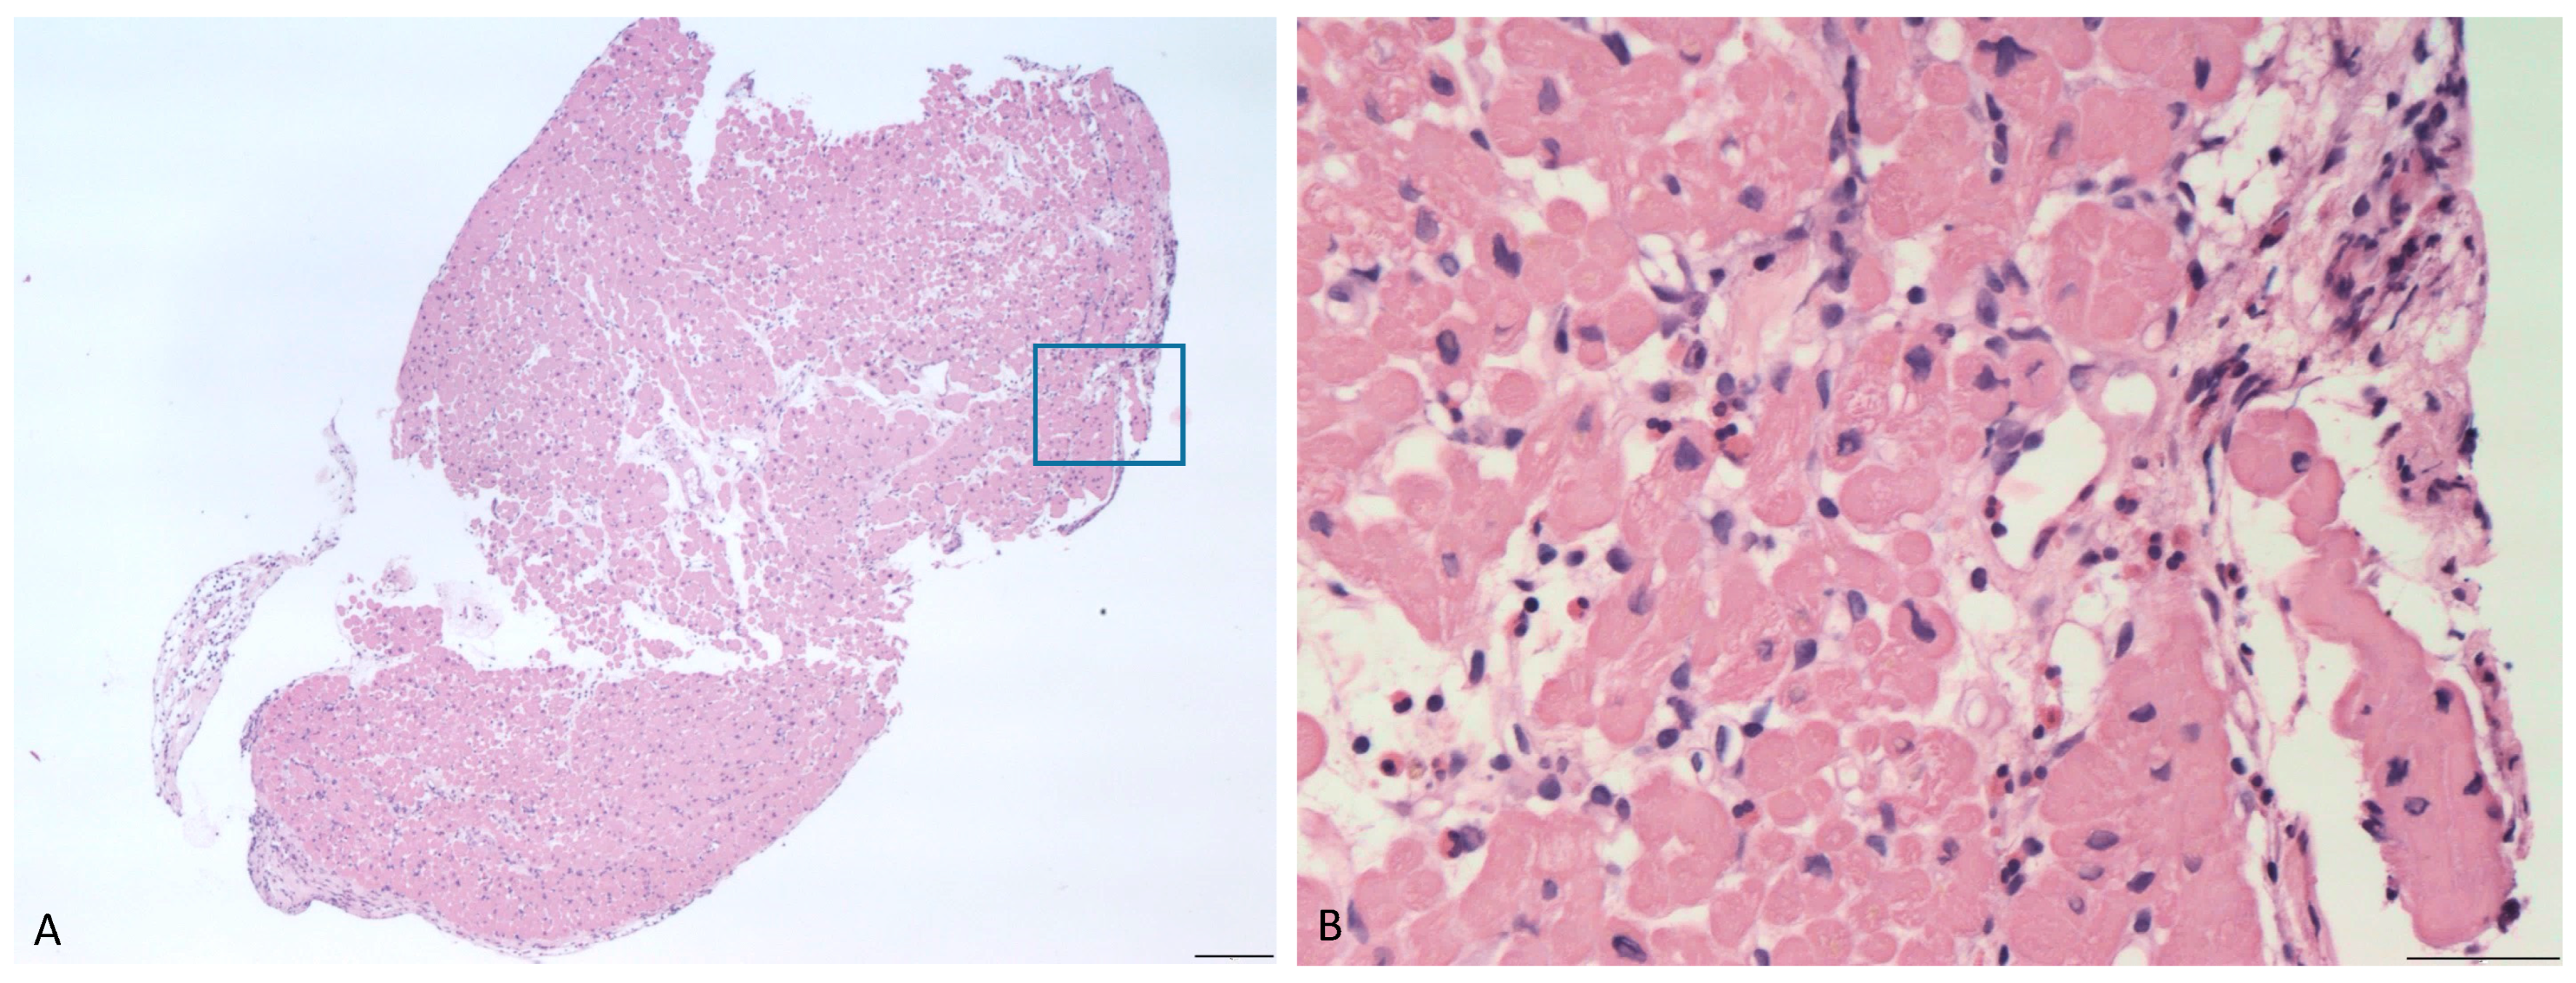

For the purposes of diagnostic confirmation, the patient underwent EMB. Histopathological findings included interstitial and perivasal myocardial infiltrates, mainly composed by lymphocytes, granulocytes and scattered eosinophils (Figure 4).

Figure 4. (A) Endomyocardial biopsy specimen, showing at higher magnification (B) an interstitial inflammatory infiltrate with eosinophils (Haematoxylin and eosin, scale bars 200 micron (A) and 50 micron (B).